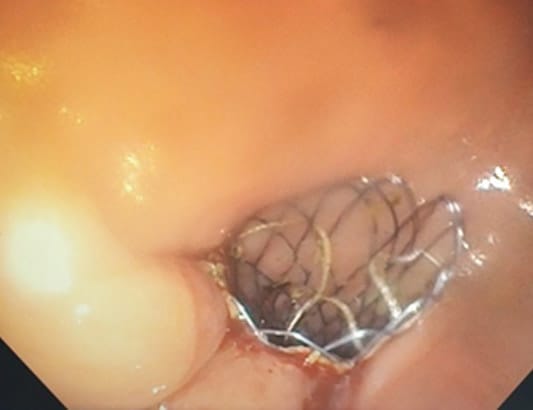

Khoa Nội tiêu hóa - Bệnh viện Quân y 175 đặt stent kim loại tự bung (semes) thành công cho bệnh nhân N.T.Đ 83 tuổi bị ung thư đại tràng Sigma đã phẫu thuật tháng 3/2020 di căn gan. Bệnh nhân được tiếp nhận vào khoa Nội Tiêu Hóa – Bệnh viện Quân y 175 với tình trạng rối loạn đại tiện kéo dài khoảng 1 tháng, thường xuyên có cảm giác mót rặn kèm đau quặn vùng hạ vị, đại tiện khó khăn, bụng chướng tăng dần.

Qua thăm khám lâm sàng, nội soi đại trực tràng kết hợp X-quang và CT-scanner ổ bụng có thuốc, các bác sĩ chẩn đoán bệnh nhân bị bán tắc ruột do ung thư đại tràng Sigma tái phát tại miệng nối di căn gan.

Trong quá trình thăm khám, Đại tá TS. BS. Trần Hà Hiếu – Chủ nhiệm Khoa Nội tiêu hóa quyết định đặt stent kim loại tự bung qua vị trí u sùi đại tràng để giải quyết lưu thông đường tiêu hóa cho bệnh nhân. Một tuần sau phẫu thuật bệnh nhân xuất viện ổn định.

Hình ảnh nội soi